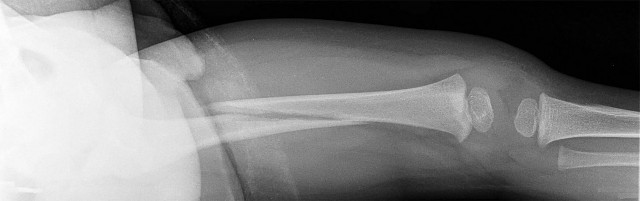

A 3-year-old boy sustains a closed, isolated, midshaft femur fracture after a fall from a playground structure.

Radiographs show 1.5 cm of overriding. What is the most widely accepted definitive management for this patient?